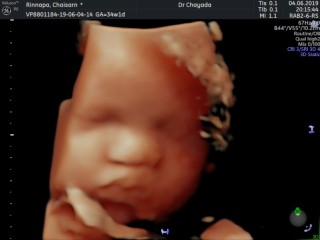

30 สัปดาห์ ลูกสาวจ้า